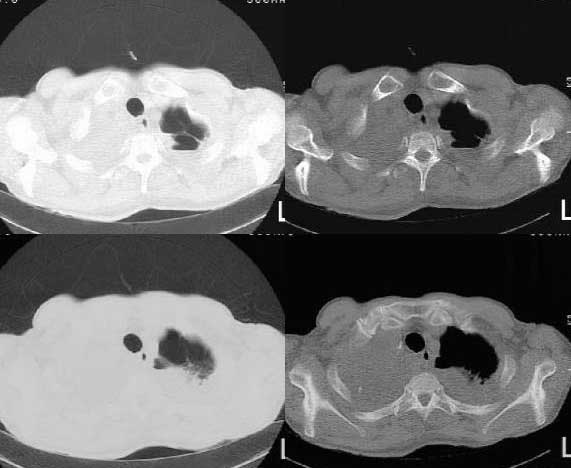

以下是引用woaixct在2006-6-23 12:15:00的发言:[br]第一张胸片示:右肺上叶为大片致密影占据,左肺上见大片致影及空洞性病灶并有液平;[br]第二张胸片示:左肺上叶致密影及空洞性病灶基本吸收,而右肺上叶之病灶有少许吸收改变;[br]ct片示:右上叶大片软组织密度,右肺门区至右肺上叶见巨大软组织块,内见支气管充气征,上纵隔右移,主气管及上叶支气受压变扁,中间支气管狭窄,左肺上叶空洞性病灶并有液平,左肺上叶尖后段见大片致密影,结合2张胸片考虑,ct片是4月份所摄,而不是6月份的片子;[br]结合2张胸片及ct片考虑:[br] 1.右中央型肺癌伴右肺上叶不张;[br] 2.左肺上叶尖后段炎性变及左肺脓肿;[br]第2张胸片提示:经过一个多月的不规则抗炎治疗,左肺上叶病灶及右肺上叶不张病灶基本吸收,而右肺占位无明显变化。

以下是引用jiangjing在2006-6-23 21:21:00的发言:[br]个人考虑还是两肺感染性病变可能大,主支气管及叶支气管是通畅的,并可见支气管气相;ct提示病变是以肺叶分布的,密度相对均匀;胸片可见有叶间裂下坠征,是不是考虑克雷伯杆菌感染可能.病人前后两张片比较病变是增多[应该考虑混合感染可能性大,右肺癌待排建议查痰及穿刺检查]